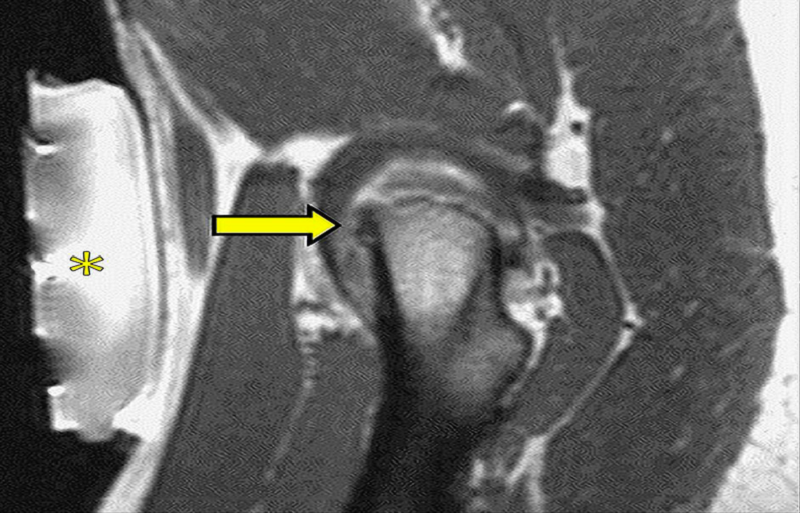

活檢和消融是在MRI引導(dǎo)下進(jìn)行的最常見的療法。主要優(yōu)點是無需造影劑即可更好地描繪目標(biāo)。實時多平面成像與高對比度分辨率相結(jié)合,可以準(zhǔn)確定位在非增強(qiáng)CT上定義不清的病灶;此外,在消融過程中,MRI允許監(jiān)測針通路和完全可視化被消融的組織,無論是在基于熱的技術(shù)(由于溫度敏感序列)和在基于冷的技術(shù)的情況下。

圖:磁共振引導(dǎo)下的復(fù)發(fā)性軟組織腫瘤冷凍消融

另一個優(yōu)點是可以連續(xù)(即使是雙傾角,典型的超聲制導(dǎo)),加上熱控制,評估燒蝕區(qū)域。